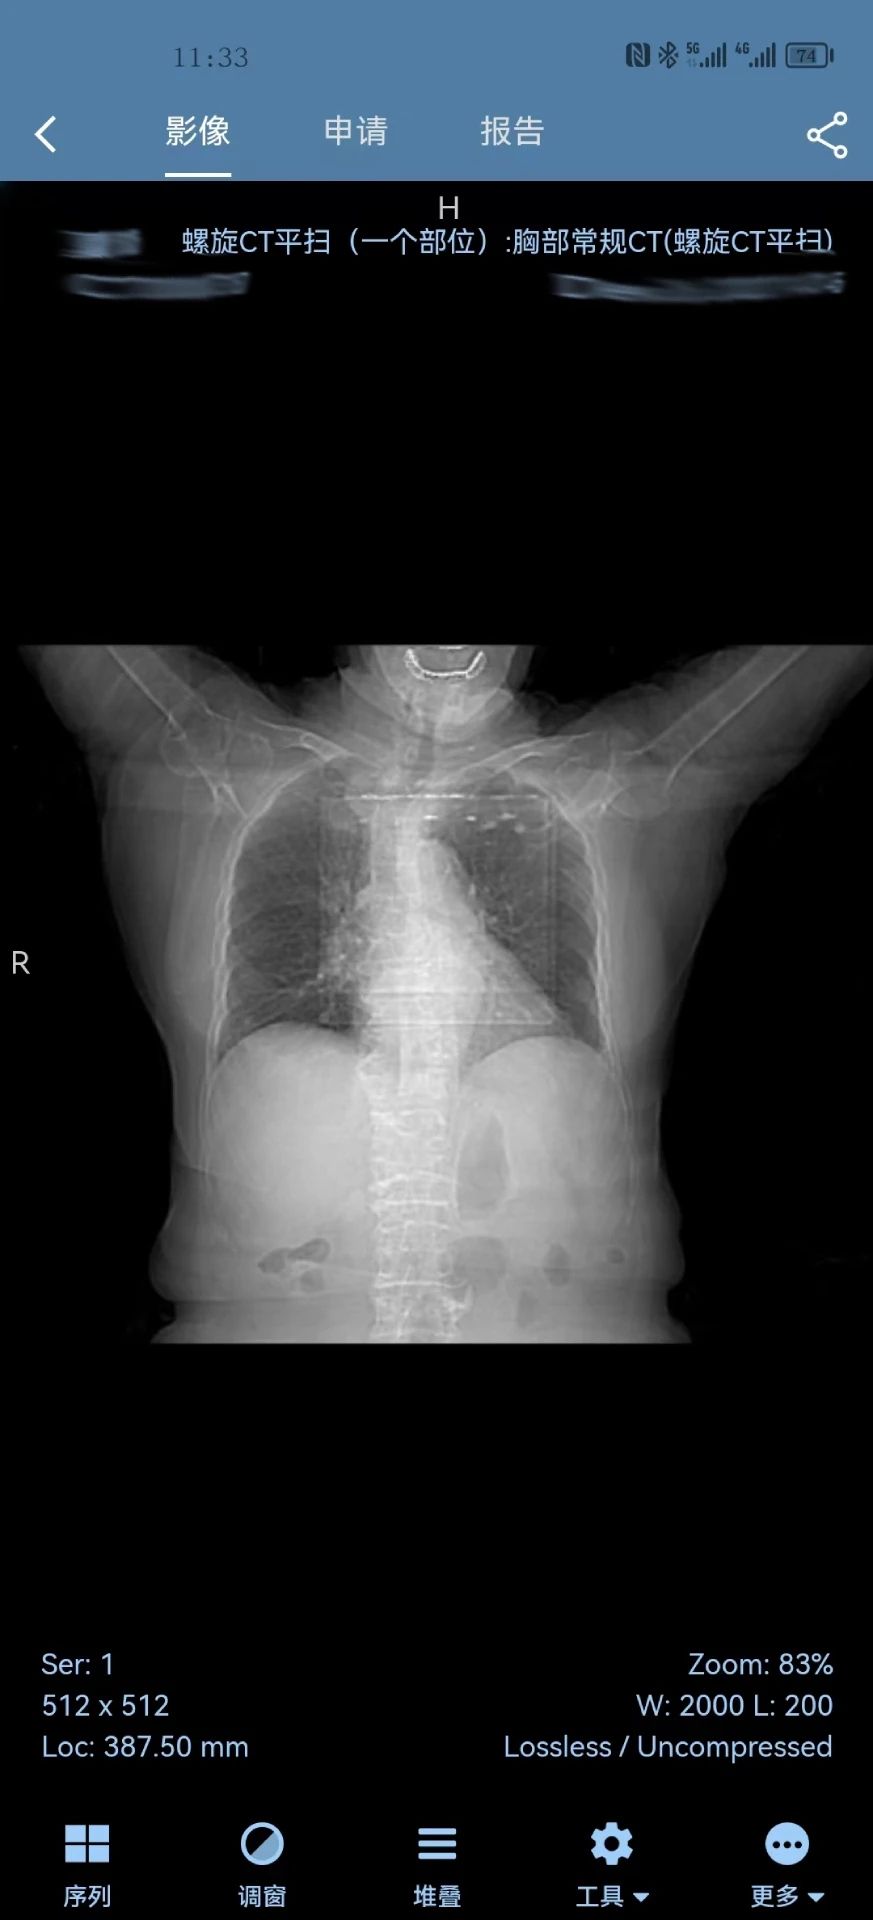

1、检查列表会显示患者当前检查部位的缩略图像,点击检查列表会进入影像查看,申请单查看,报告书写界面。

2、影像查看与操作分云端处理和本地无损、本地有损处理三种模式,不同之处是,云端处理消耗流量较小,但操作图像会有一定的延迟。

3、本地处理模式会消耗较多流量,操作图像不会有任何延迟,如同本地工作站一样。报告单提供了完整的影像科报告书写流程。